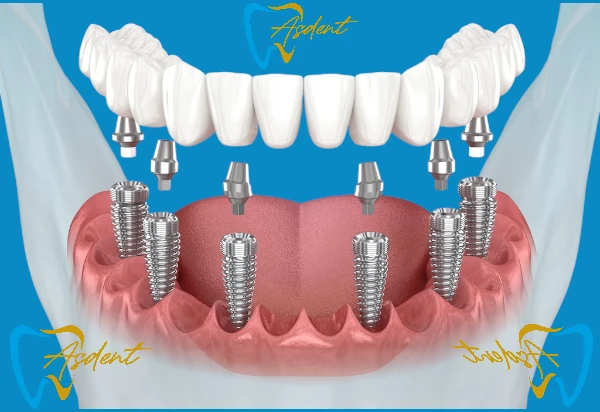

All-on-4 İmplant Paketi /ASDENT Bursa İnegöl

- 4 implant üzerine sabit protez sistemi

- Geçici protez ile aynı gün gülümseme

- Nihai porselen ya da zirkonyum protez

- Gerekli radyolojik görüntüleme ve muayene

- Tüm ilaçlar, kontroller ve cerrahi bakım dahil

Avantajları: Daha az implantla tam çene sabit protez, hızlı sonuç, maliyet avantajı.

All-on-6 İmplant Paketi /ASDENT Bursa İnegöl

- 6 implant ile tam çene sabit dişler

- Daha dayanıklı ve uzun ömürlü sonuçlar

- Gerekli röntgen, tomografi ve konsültasyon

- Tedavi sonrası düzenli kontrol randevuları

Avantajları: Daha fazla implant ile ekstra sağlamlık ve uzun vadeli konfor.

All-on-8 İmplant Paketi /ASDENT Bursa İnegöl

- 8 implant ile desteklenen tam diş arkı sabit protez

- Maksimum dayanıklılık ve uzun ömürlü sonuçlar

- Panoramik röntgen, 3D CBCT taraması ve ayrıntılı konsültasyon dahil

- Tedavi sonrası düzenli takip randevuları

Avantajlar: 8 implant sayesinde çene kemiği üzerinde eşit kuvvet dağılımı, Ekstra güç, konfor ve uzun vadeli başarı, Doğal dişlere en yakın estetik ve fonksiyonel sonuç.